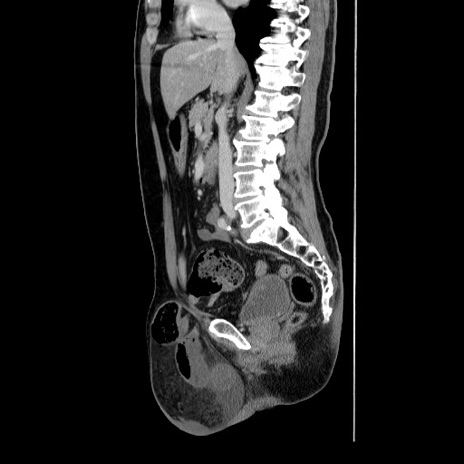

症例34(矢状断像)

【症例】60歳代 男性

【主訴】右鼠径部膨隆

【現病歴】1年程前より右鼠径部膨隆あり。自己にて還納可能だったため放置していた。3時間前より右鼠径部の脱出を認め、還納困難となり受診。

【身体所見】右鼠径部に小児頭大の膨隆あり。弾性硬であり、用手還納は困難。左鼠径部にも膨隆を認める。脱出はなし。